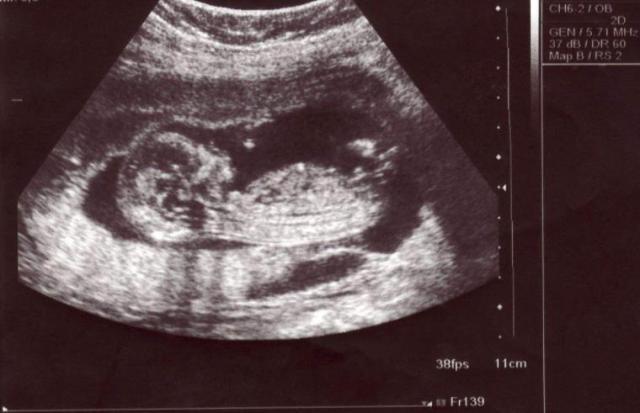

怀孕期间,孕妈最担心宝宝发育期出现异常,其中最典型的几个症状,无非就是胎儿流产、胎儿畸形、脐带绕颈、胎儿缺氧、胎儿窒息、早产、胎停育等问题。

今天就讲其中一项,就是脐带绕颈,一旦脐带绕颈之后,缠绕周数过多过紧的话,会造成胎儿缺氧,甚至可能会造成胎儿窒息,出现胎停育问题。

脐带绕颈,发生在出现胎动之后,因为出现胎动之后,胎儿在子宫内的活动频率就增加了,就很可能会造成脐带缠绕,进而出现脐带绕颈问题。

为了有效预防脐带绕颈,孕妈除了要注意各种孕期晋级之外,还应该牢记脐带绕颈后的一些症状。孕期,若出现了脐带绕颈的情况,孕妈会有什么症状?